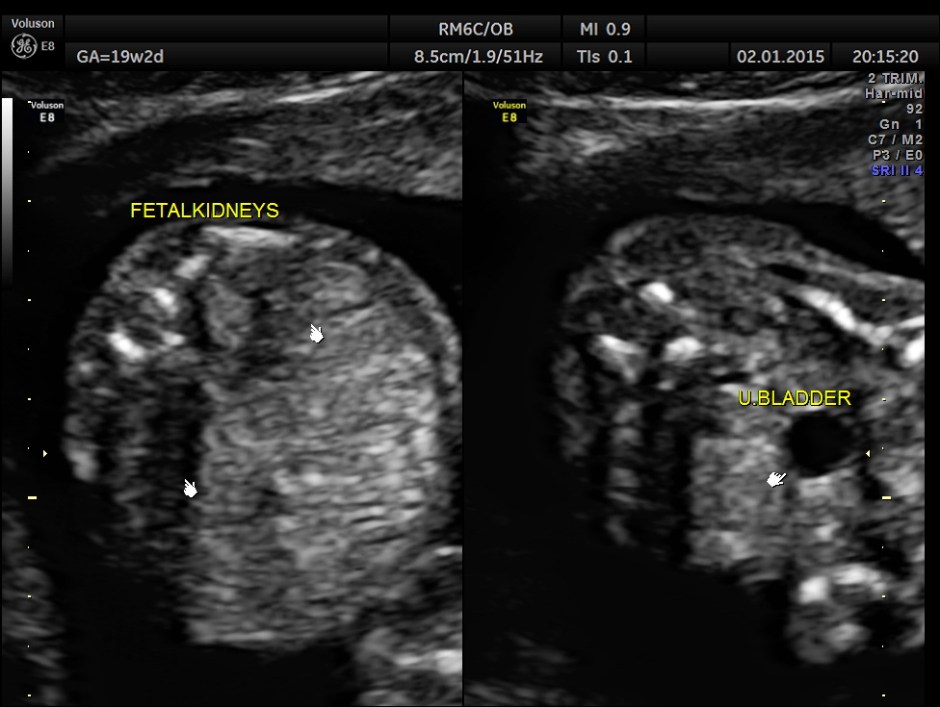

The rest of the scan findings were normal.